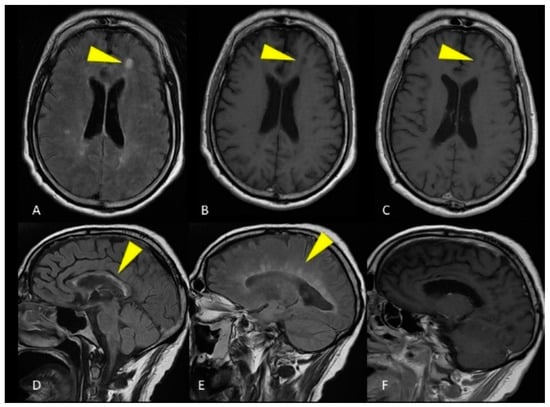

2.1. Case Presentation 1